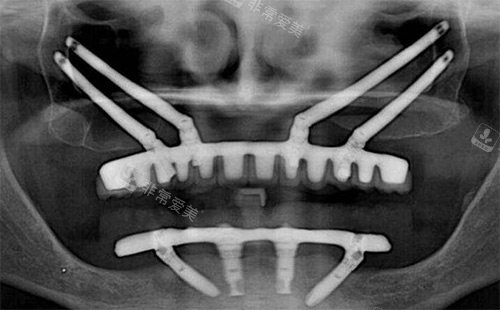

穿颧穿翼种植拍片

森朗口腔特别擅长穿颧穿翼种植技术,这是针对骨量重的不足患者的解决方案。

传统种植需要先植骨,等待6个月才能种植,而穿颧穿翼技术可以直接植入,大大缩短治疗周期!